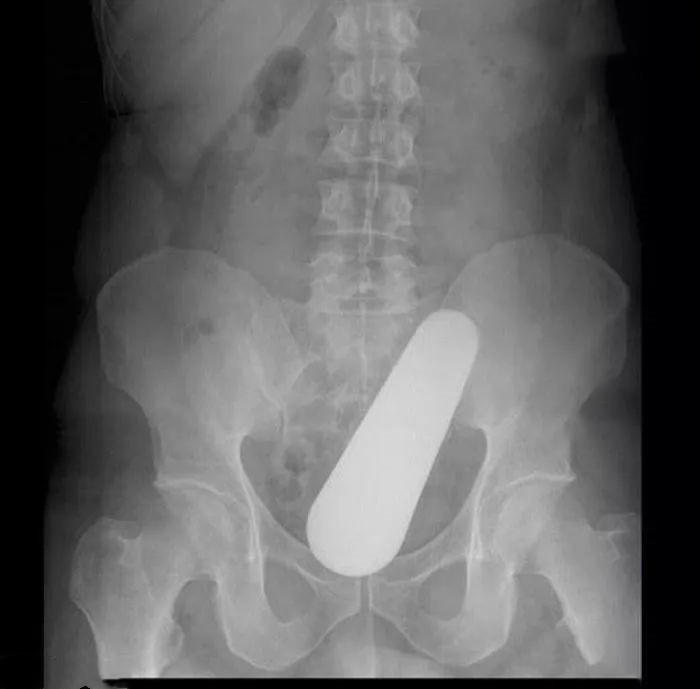

这是一名 40 多岁男人的 “内部构造”,这个黄瓜状的物体,他声称是在泰国旅游休闲时不小心弄到体内的。